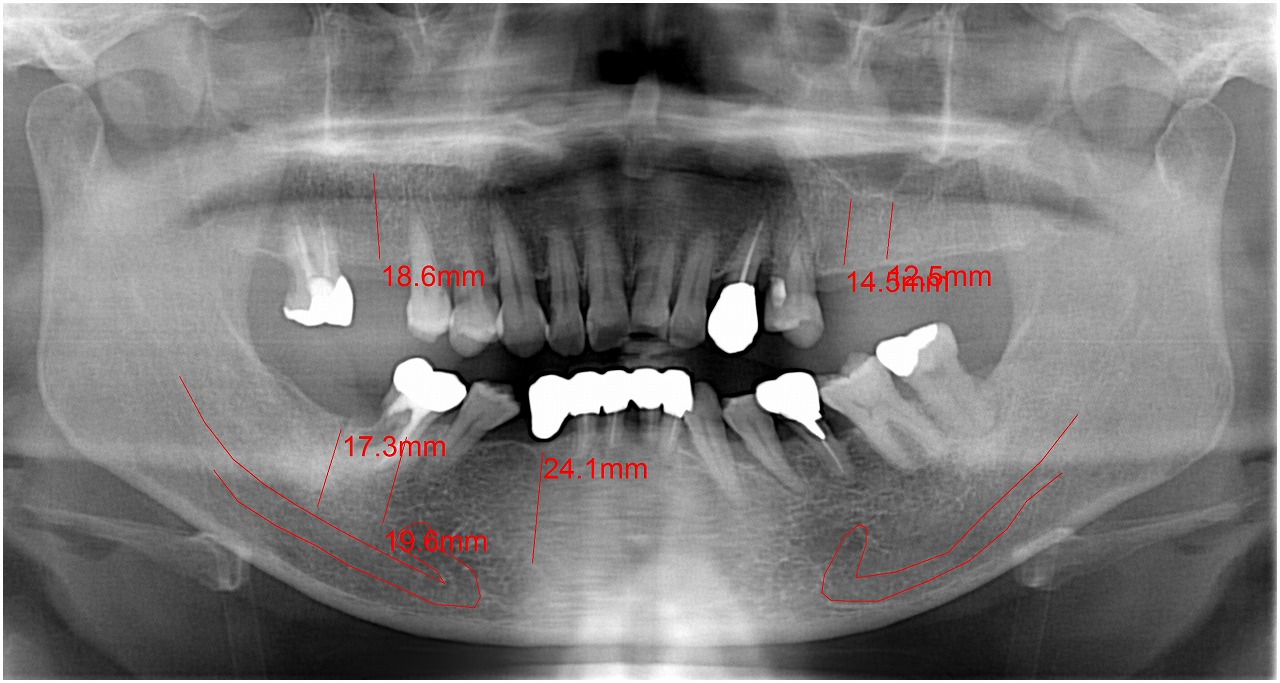

お知らせ|広島市安佐南区の歯科医院 > お知らせ トップ お知らせ・ブログ お知らせ スタッフブログ お知らせ お知らせ 2024/12/14 左上のインプラント埋入からの最終補綴までの流れ お知らせ 2024/12/14 左上の5,6,7番部へインプラント埋入をおこなっていきます お知らせ 2024/12/13 右下のインプラント部の最終補綴までの流れ お知らせ 2024/12/13 欠損部へインプラントを用いて咬合再構成をおこなった1症例 お知らせ 2024/12/12 審美領域のインプラント治療の臨床現場 最終補綴までの流れ お知らせ 2024/12/12 左上の1番部の破折 ブリッジかインプラントか? インプラントを選択 お知らせ 2024/12/11 右下のほぼ見えていない歯の親知らずの難抜歯 臨床現場ではこういった歯も要望に合わせて抜歯していきます お知らせ 2024/12/11 右下の親知らずの難抜歯 親知らず難抜歯の臨床現場 お知らせ 2024/12/10 左下の奥 親知らずの難抜歯 近くの歯医者では抜いてくれないと、、、 お知らせ 2024/12/09 左上の4番部のインプラント埋入から3か月 インプラント部の最終補綴が入るまでの工程になります << 1 2 3 4 5 … 11 12 13 14 15 … 485 486 487 488 489 >> Web診療予約 初めての方へ 選ばれ続ける理由 院内設備について 歯が痛いしみる一般歯科 歯がぐらぐらする歯周病 健康な歯を保ちたい予防歯科 子供の虫歯予防をしたい小児歯科 銀歯をセラミックに審美歯科 白い歯を目指しませんか?ホワイトニング 矯正専門医がいるので安心矯正歯科 抜けた歯を補いたいインプラント・入れ歯 医院案内 スタッフ紹介 メリィハウス歯科クリニックオフィシャルホームページ ラベンダー歯科クリニックオフィシャルホームページ お知らせ・ブログ ホーム 診療科目 一般歯科 歯周病治療 予防治療 小児歯科 審美治療 ホワイトニング 矯正歯科 入れ歯・インプラント マウスピース矯正 初めての方へ 院長・スタッフ 設備紹介 医院案内・アクセス メニューを閉じる